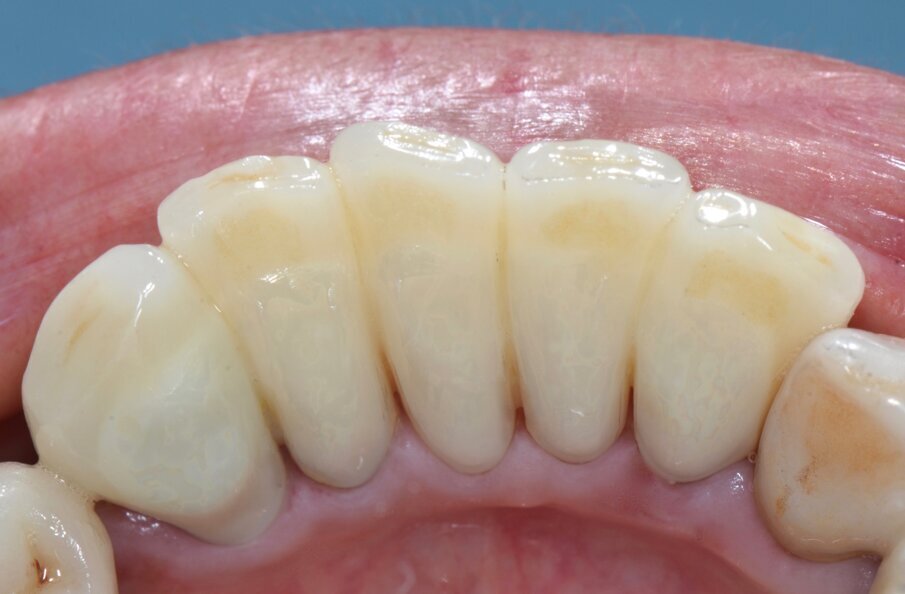

Riguardo al comparto intraorale, dalle radiografie diagnostiche e dall’esame parodontale e occlusale sono emersi aspetti che meritavano una correzione anche nei settori posteriori, ma la paziente ha deciso di effettuare inizialmente il trattamento dei soli gruppi frontali superiore e inferiore demandando a un momento successivo le problematiche dei quadranti posteriori (Figg. 2-6). Nel gruppo frontale superiore si possono notare recessioni gengivali sugli incisivi centrali, che sono anche molto ruotati, e sul canino di sinistra; corone in metallo-ceramica sugli incisivi laterali con esposizione del bordino metallico e una corona in ceramica metal-free sul canino di destra. Inoltre è molto evidente lo squilibrio delle parabole gengivali tra i due canini, per cui per ristabilire un’estetica ottimale sarà necessario anche interessare i tessuti molli eseguendo una chirurgia resettiva sul canino di destra e, al contrario, un lembo a posizionamento coronale sul canino di sinistra (Fig. 7).